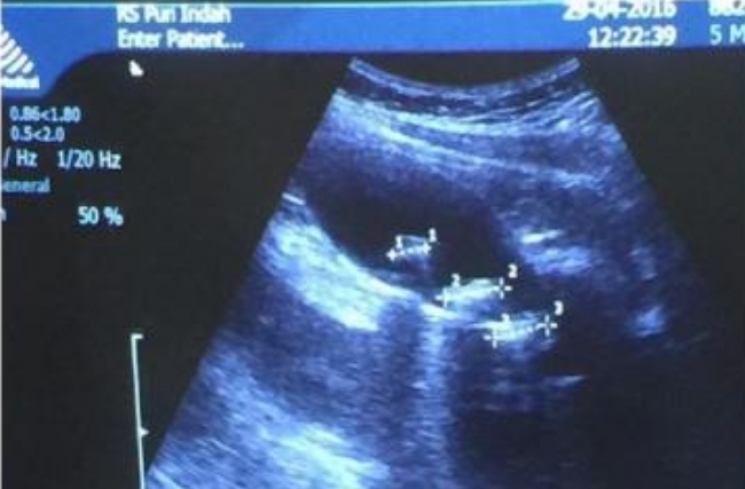

Namun dulu pada tahun 2016, Maia Estianty pernah curhat di akun Instagramnya kalau ada gangguan pada empedunya.

Ditemukan tiga batu empedu berukuran 1,5 cm yang berpengaruh pada asam lambungnya. Waktu itu pun Maia Estianty sempat dioperasi.

"Ditemukan 3 batu di empedu saya sebesar 1,5 cm. Mustinya koleksi batu berlian, eh, ini dikasih anugerah batu empedu. Pantesan asam lambung saya kumat tiap hari. Kemungkinan akan dioperasi," curhat Maia tahun April 2016 lalu.